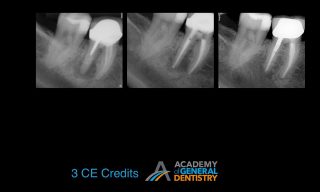

According to literature, the survival rate of endodontically treated teeth is close to 98%. How do we update our understanding of endodontics so that we can care for our patients and close in on the 98% published survival rate? The most common reason for a failed root canal treatment is inadequate treatment. However, there are some cases in which a root canal treatment is carried out in accordance with the highest standards, and yet still results in failure. In most such cases, the endodontic failure results from persistent intra-radicular infection. In other cases, extra-radicular infections and intrinsic or extrinsic non-microbial factors might be implicated in the failure.

The purpose of this lecture is to discuss the etiological factors of failed root canal treatments using a series of clinical cases. It will aid clinicians in choosing between surgical and non-surgical management of a failed root canal in an evidence-based manner. Indications for the non-surgical vs. surgical retreatment of failed endodontic cases are discussed in order to maximize the success of an endodontic retreatment.